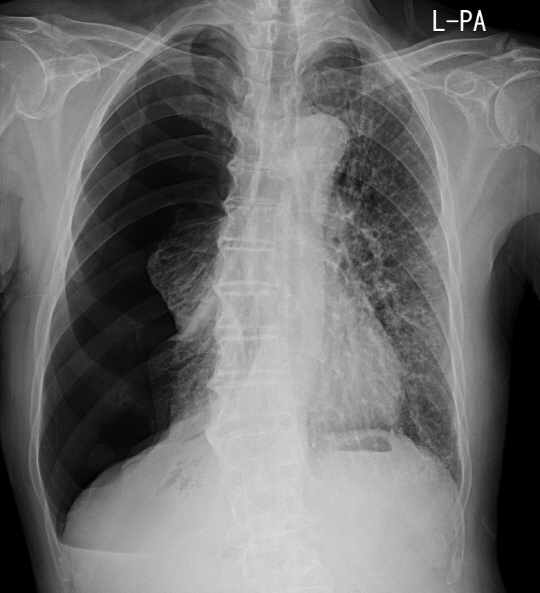

기흉의 발생 여부는 X-Ray를 통해 쉽게 확인해 볼 수 있다. 환자가 산소를 호흡해 증상이 자연스럽게 줄어들도록 하는 산소치료는 경미한 질환자를 대상으로 한다. 최근에는 흉막강 내에 튜브를 삽입해 고여 있는 공기를 제거하는 방법 또한 자주 시행되고 있다. 증상이 심각하거나 재발된 경우에는 수술이 시행되기도 한다. 수술을 하지 않을 경우 재발율이 50%에 달하는 기흉의 질환적 특성상 수술을 통한 치료는 더욱 일반화될 전망이다.